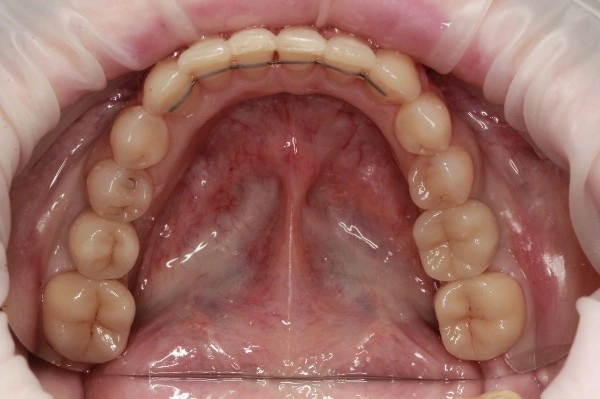

Установлены 2 коронки на импланты с индивидуальным циркониевым абатментом. На задние сильно разрушенные жевательные зубы установлены керамические накладки.

Работа врача - ортодонта Глуховой Татьяны Александровны и врача - ортопеда Никитина Никиты Юрьевича.